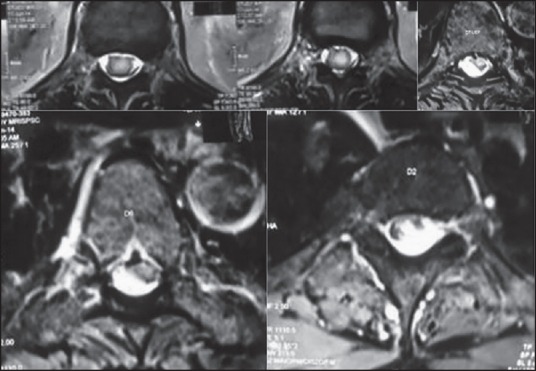

Figure 3.

Axial sections of the different levels of metastasis

MRI of the brain was not suggestive of tumor at the primary site. Pre and postcontrast MRI of the spine showed a 24 mm × 9 mm × 11 mm ill-defined, enhancing, intramedullary lesion at D2-3 with cord expansion with extension into the extramedullary space with diffuse leptomeningeal involvement all along the cervical spine, along the filum and conus [Figures 2 and 3]. He underwent D2-6 laminectomy and tumor decompression, histopathology of which was suggestive of high grade astrocytoma compatible with recurrent metastatic glioblastoma (WHO grade IV). The patient then underwent radiotherapy which he could not tolerate and eventually succumbed to his disease after a period of 6 months.